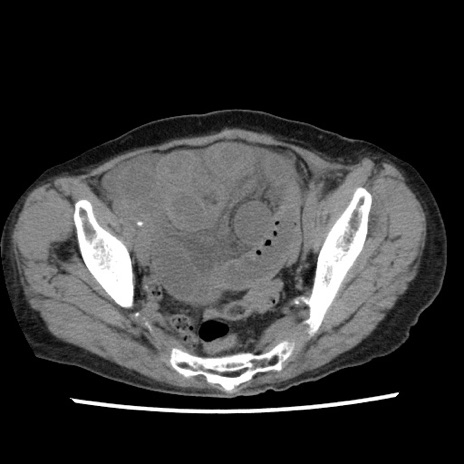

【症例】80歳代女性

【主訴】腹痛

【現病歴】8時間前から腹痛あり来院。

【既往歴】糖尿病、脂質異常症、子宮体癌にて子宮全摘術

【身体所見】意識清明・会話良好だが腹痛で苦悶様、全腹部にわたって反跳痛と圧痛あり

【データ】WBC 13600、CRP 0.14、LDH 224、CK 90